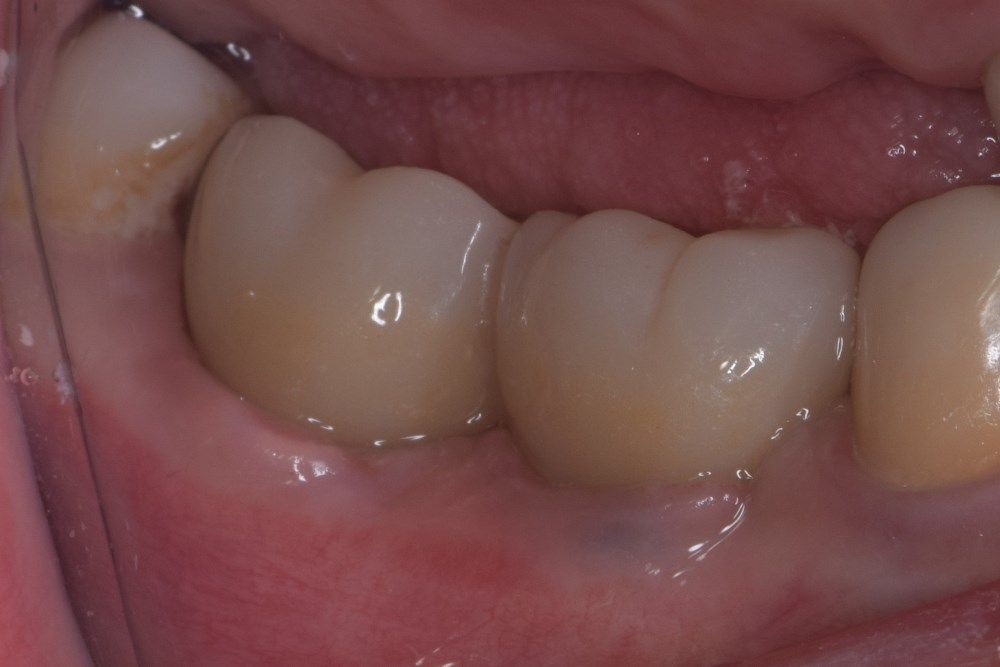

фото коронок

Имплантация жевательных зубов,

это самая востребованная операция.

после

до